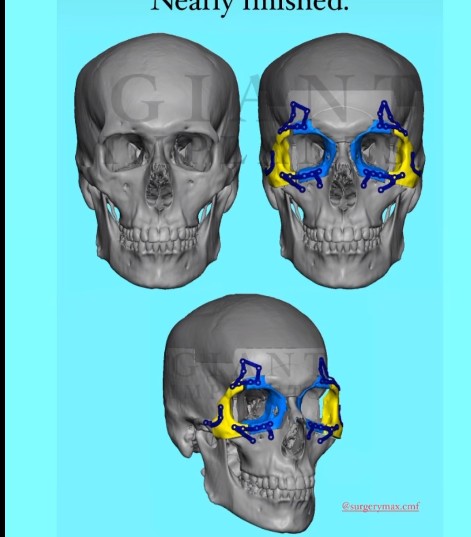

3. OBO(Orbital box osteotomy)

3. OBO(Orbital box osteotomy)